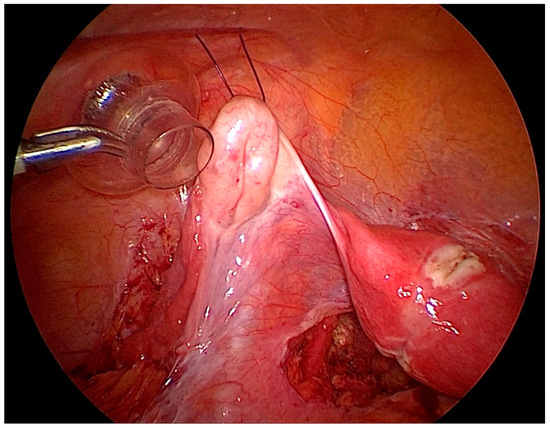

After gaining access to the peritoneal cavity laparoscopically (Figure 1), the cavity is thoroughly investigated for endometriotic cysts, spots, and adhesions. If an endometriotic ovarian cyst is found, it is excised. If endometriotic spots or nodules are found underneath the ovary on the ovarian fossa, or uterosacral ligaments, the ipsilateral ovary is suspended to the anterior abdominal wall (Figure 2). A straight needle with a single monofilament non-absorbable thread is passed through the lower anterior abdominal wall. Prior to insertion of the needle, the inferior epigastric vessels should be located to avoid injury and hematoma formation. The needle is retrieved intra-corporeally by grasping it using a laparoscopic needle holder. It is then passed from the medial side of the ovary through the ovary into the abdominal wall close to the point where it was introduced. At this step also, it is essential to pay attention to the inferior epigastric vessels once more. The needle is then pulled out from the abdominal wall using a hemostat forceps. The two ends of the thread are tied extra-corporeally over a compressor gauze on the abdominal wall, with some tension, thus suspending the ovary to the abdominal wall with the medial side of the ovary apposed to the peritoneum of the anterior abdominal wall (Video S1).

Figure 1. Laparoscopic view of the pelvis, depicting the ovaries hampering vision and access to the lateral pelvic wall.